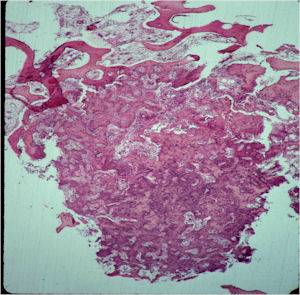

Microscopic Pathology

- The nidus of an osteoid osteoma consists of vascularized fibrovascular stroma and trabeculae of immature woven bone

- Nidus is sharply demarcated from surrounding reactive bone and there is an abrupt zone of transition between normal bone and the osteoid osteoma. There is no permeation of the lesion through the surrounding reactive trabeculae of bone,

- The trabeculae are uniformly lined by plump, uniform, active osteoblasts (“Osteoblastic Rimming)

- Osteoclasts may be prominent

- Mature nidus consists of more heavily calcified trabeculae of woven bone and osteoid

- No abnormal mitoses